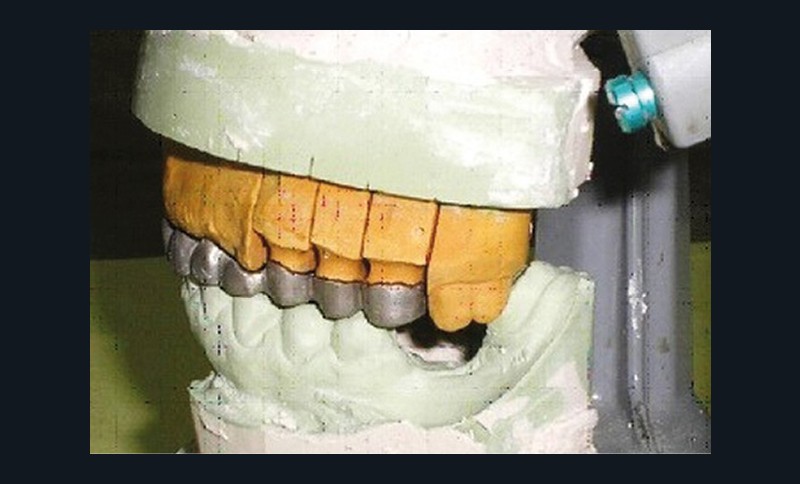

Analyse sur articulateur : les moulages d’étude transférés par le biais d’un arc facial sur articulateur semi-adaptable à la bonne dimension verticale d’occlusion sont analysés.

- Cire de diagnostic : le wax-up, ou cire de diagnostic, a été effectué (fig. 7). Ce guide référentiel thérapeutique permet de concrétiser le projet prothétique d’un point de vue esthétique et fonctionnel ; il constitue un outil indispensable de communication à la triade patient/praticien/prothésiste [10-12].

Confection de la prothèse d’usage : la prothèse transitoire est restée deux mois en bouche, jusqu’à l’intégration fonctionnelle et la satisfaction esthétique de la patiente [13,14]. Puis, la prothèse d’usage est confectionnée, en commençant par la réalisation de l’armature métallique au laboratoire (fig. 13a-h).

La phase suivante consiste à l’essayage clinique des armatures qui permet de contrôler la précision de leur adaptation cervicale, les épaisseurs métalliques et l’ouverture des embrasures (fig. 14) [15].